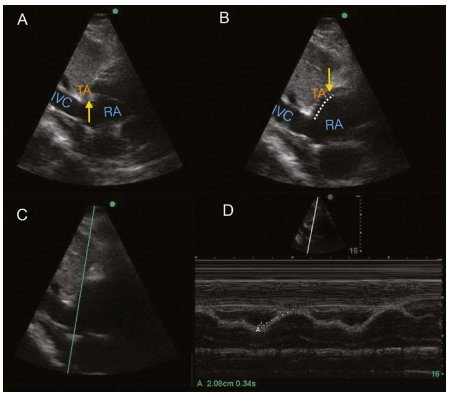

6⃣ @Jose_Diaz_Gomez et. al. also developed SEATAK (subcostal echocardiographic assessment of tricuspid annular kick) - essentially a TAPSE from the subcostal view. Useful, validated, and also an example of thinking critically about what we see on echo to develop new techniques.